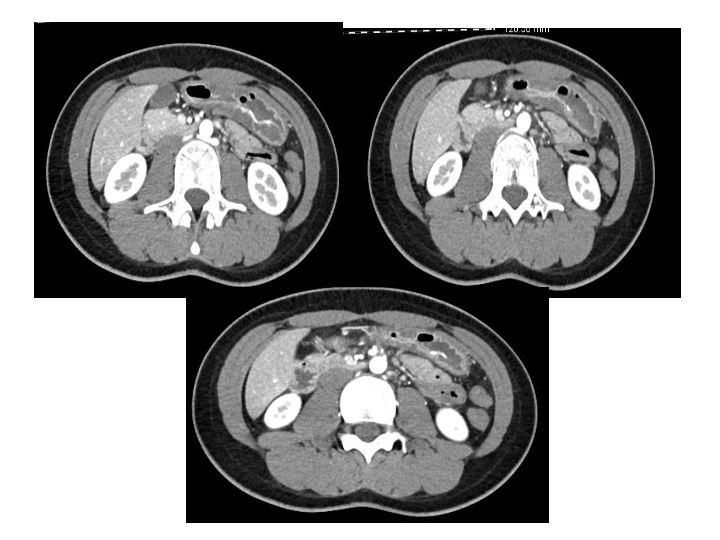

腹部创伤的救治案例